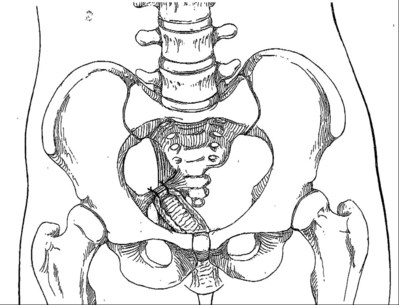

The endopelvic fascia is a network of fibromuscular tissue located between the peritoneum and the levator muscles. It surrounds and attaches the bladder, uterus, vagina, and rectum to the pelvic walls, thereby stabilizing the pelvic viscera. The endopelvic fascia is one continuous unit; however, distinct areas are named separately. The parametrium (broad, cardinal, and uterosacral ligaments) attaches the uterus and upper vagina to the pelvic sidewall. The paracolpium (the arcus tendineum levator ani and the ATFP) attaches the vagina to the pelvic sidewalls. In his landmark article, DeLancey (1992) described the supports of the vagina and conceptually divided them into three parts according to the region of vaginal support (Fig. 72–6). The structures supporting the uterus and the cephalad 2 to 3 cm of the vagina comprise level I support, and these fibers originate from the greater sciatic foramen, the sacroiliac region, and the lateral sacrum. The fibers are primarily vertical in their orientation and are the longest fibers of the endopelvic fascia, thereby suspending the uterus and upper vagina, and comprise the cardinal/uterosacral ligament complex. Level II support is at the mid vagina. These fibers are shorter than level I support but longer than those at level III. The orientation of the attaching fibers is lateral, and they are more dense than the cardinal/uterosacral ligament complex. The endopelvic fascia splits at this level to encompass the bladder and urethra such that the abdominal leaf is still named the endopelvic fascia and the vaginal leaf is the pubocervical and periurethral fascia. Posteriorly, the endopelvic fascia, which attaches laterally to the superior fascia of the levator ani muscles, is the rectovaginal fascia. Level III support of the vagina starts at the introitus and extends 2 to 3 cm above the hymenal ring. In this most distal location there is no intervening paracolpium and the vagina is fused directly to the urethra and is embedded in the connective tissue of the perineal membrane (urogenital diaphragm). Laterally it blends into the medial margins of the levator ani muscles, and posteriorly it blends into the perineal body.

Figure 72–6 Vaginal and visceral supportive structures as defined by DeLancey. The fibers of level I support are oriented vertically and suspend the uterus and upper vagina. Level II support is more horizontal in its orientation and attached to the mid vagina. Distally, level III support fuses directly into the support structures.

(From DeLancey JO. Anatomic aspects of vaginal eversion after hysterectomy. Am J Obstet Gynecol 1992;166:1717–28.)